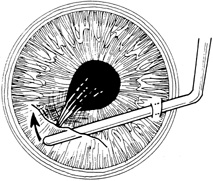

Incarcerated tissue will usually require mechanical reposition. Selected cases of mild incarceration may be treated with pharmacologic agents. Agents such as intraocular acetylcholine or carbachol cause pupil constriction, thus pulling iris from the wound. If incarcerated iris is located in the central cornea, mydriatic agents (e.g., intraocular epinephrine 1:10,000) may be used. If mechanical reposition is required, simply deepening the anterior chamber may release incarcerated tissue. Viscoelastic agents may be irrigated through the paracentesis port or the wound adjacent to the involved iris tissue in an attempt to draw the incarcerated iris from the wound (Fig. 12). If unsuccessful, a cyclodialysis spatula or irrigating canula may be passed through the paracentesis site and used to directly sweep incarcerated tissue free (Fig. 13). Care is always taken to avoid trauma to the corneal endothelium, iris, and lens. Any excised tissue should be sent to the pathology department for examination.